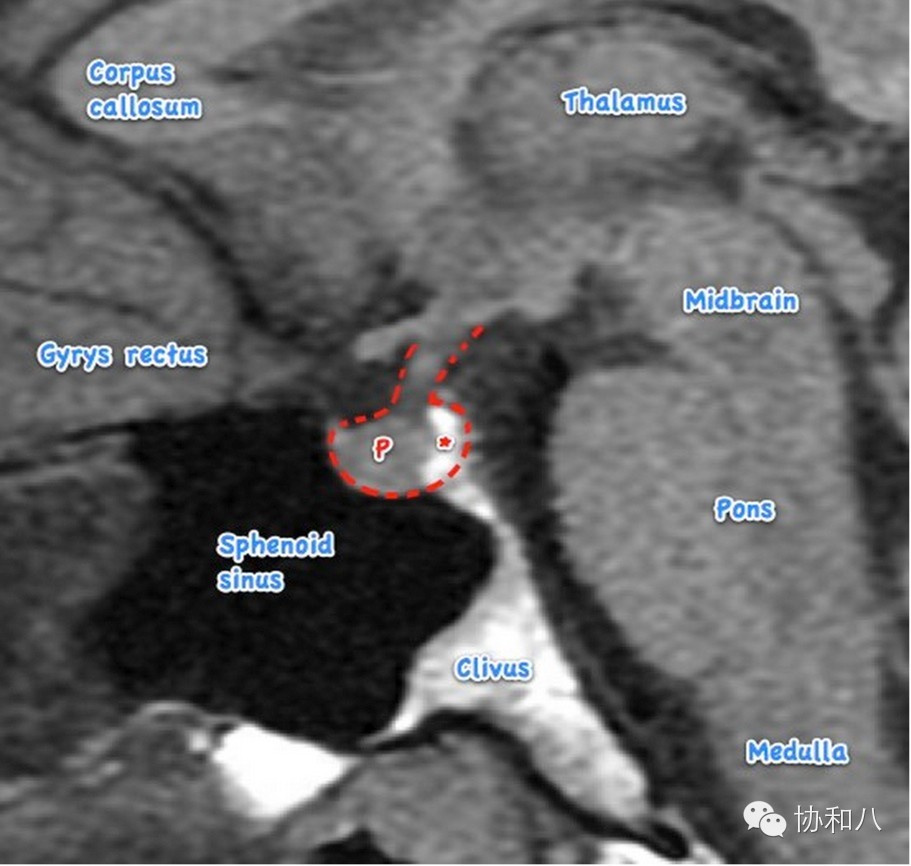

A.正中矢状位MRI T1W1

Corpus callosum-胼胝体;Gyrus rectus-直回;sphenoid sinus-蝶窦;Clivus-斜坡;Medulla-延髓;Pons-脑桥;Midbrain-中脑;Thalamus-丘脑;P-垂体前叶;*-垂体后叶。